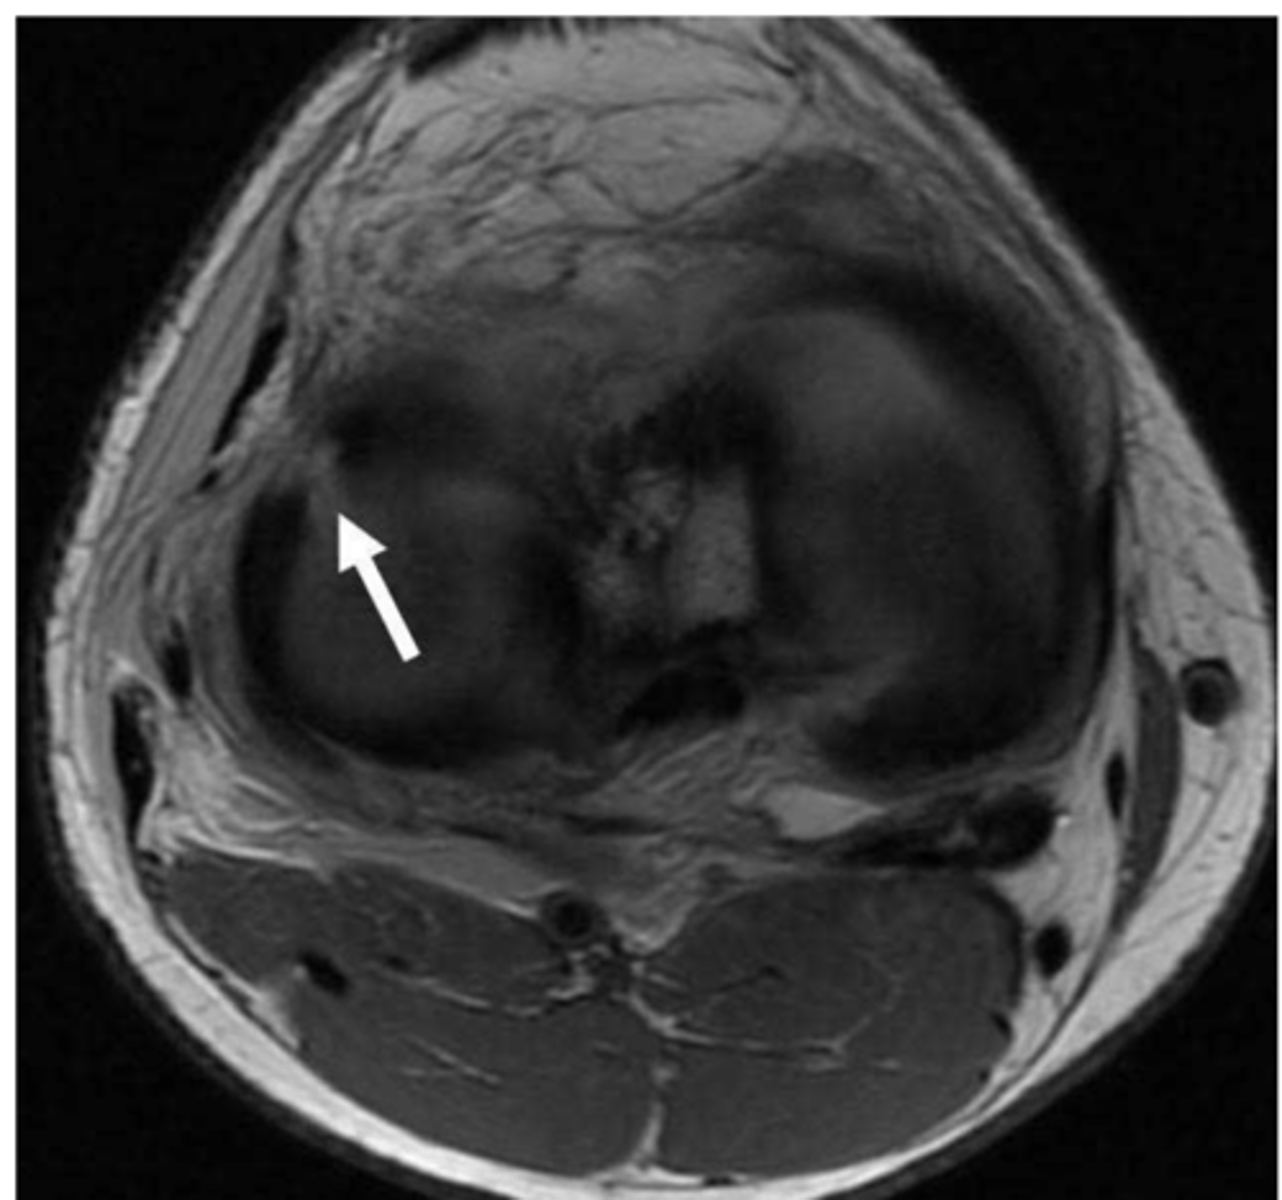

Meniscus tear

Define the pathology.